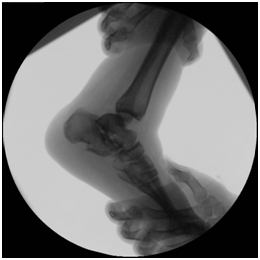

Treatment Management began with stabilization of the patient’s general condition, and later definite treatment on 2nd stages. 1st stage: Patient went for decompression spine surgery and examination under anesthesia (EUA) of the right ankle which demonstrated medial and lateral ligament complex instability as evident by a positive anterior drawer test (Figure 3), a posterior drawer test (Figure 4) and a positive varus and valgus stress tests with intact syndesmosis clinically (Figure 5 & 6). Because of the local swelling, the patient was put in a cast. 2nd stage: 5 days later, when the swelling subsided, patient underwent open reduction internal fixation of the right calcaneus fracture and repair of the medial and lateral ligament complex tears.

Figure 3 Anterior drawer test: an anteriorly directed force is applied to the heel while supporting the leg.

Figure 4  Posterior drawer test: a posteriorly directed force is applied to the foot while supporting the leg.

Figure 5 Varus stress test: Varus force is applied to the ankle. The ankle joint open up laterally.

Figure 6 Valgus stress test: Valgus force applied to the ankle. The ankle opens up medially.